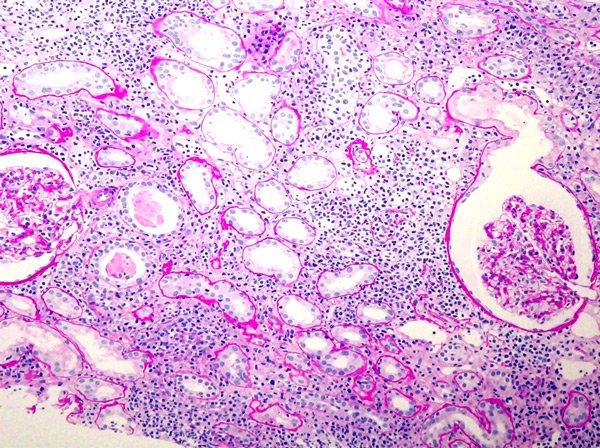

fig.3 Ä“ü‰@ŽžPASõF